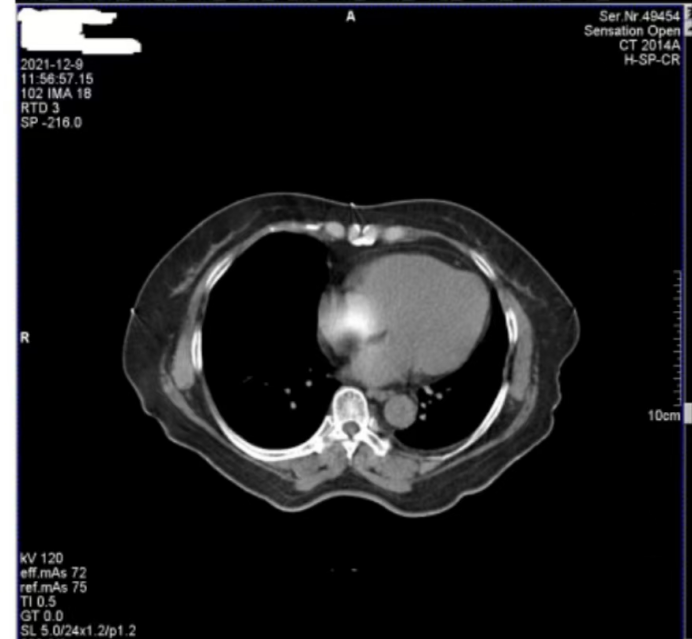

醫(yī)院反映,西門子Definition型CT機(jī)在進(jìn)行患者掃描時(shí),圖像上會(huì)偶發(fā)兩種偽影。一種是斜線狀偽影(圖 1),另一種是中心不規(guī)則高密度偽影(圖 2)。其中,斜線狀偽影對(duì)診斷影響較大,時(shí)常導(dǎo)致醫(yī)生無(wú)法準(zhǔn)確判斷患者病灶情況,醫(yī)院希望我們盡快排查并解決問(wèn)題。

圖2

接著,我們將目光轉(zhuǎn)向圖 2 中的中心不規(guī)則高密度偽影。為了找出偽影成因,我們對(duì)設(shè)備的多個(gè)關(guān)鍵部件進(jìn)行了檢查。首先查看了玻璃條、探測(cè)器表面以及準(zhǔn)直器表面,確認(rèn)這些部位是否沾有造影劑,因?yàn)樵煊皠埩粲袝r(shí)會(huì)導(dǎo)致偽影產(chǎn)生,但檢查結(jié)果顯示這些部位均干凈無(wú)污。

隨后,我們檢查了特氟龍濾線器部件。特氟龍部件采用金屬材質(zhì),具有較高的穩(wěn)定性,通常不會(huì)出現(xiàn)斷裂等情況,因此可以排除因特氟龍部件異常導(dǎo)致偽影的可能??紤]到這種中心偽影是偶發(fā)出現(xiàn)的,我們開始推測(cè)其他可能性。結(jié)合球管的結(jié)構(gòu)和工作原理,我們懷疑是球管內(nèi)部存在雜物。球管內(nèi)部有油路循環(huán)系統(tǒng),若有雜物混入其中,在曝光過(guò)程中,當(dāng)雜物恰好處于出射線的位置時(shí),就會(huì)對(duì)射線產(chǎn)生干擾,從而在圖像中心形成不規(guī)則的高密度偽影。

綜合以上分析,圖 1 中的斜線狀偽影由球管打火引起,且已嚴(yán)重影響診斷;圖 2 中的中心偽影雖成因未完全確定,但推測(cè)與球管內(nèi)部雜物有關(guān)。鑒于球管打火問(wèn)題的嚴(yán)重性以及兩種偽影可能存在的關(guān)聯(lián)性,我們判斷需要更換球管來(lái)徹底解決問(wèn)題。

此次維修案例中,更換球管后兩種偽影均消失的結(jié)果,不僅證實(shí)了圖 1 中斜線狀偽影由球管打火導(dǎo)致的判斷,也驗(yàn)證了我們對(duì)圖 2 中心偽影成因的推測(cè)是正確的,即球管內(nèi)部雜物在油路循環(huán)過(guò)程中,于曝光時(shí)處于出射線位置而造成了中心偽影。